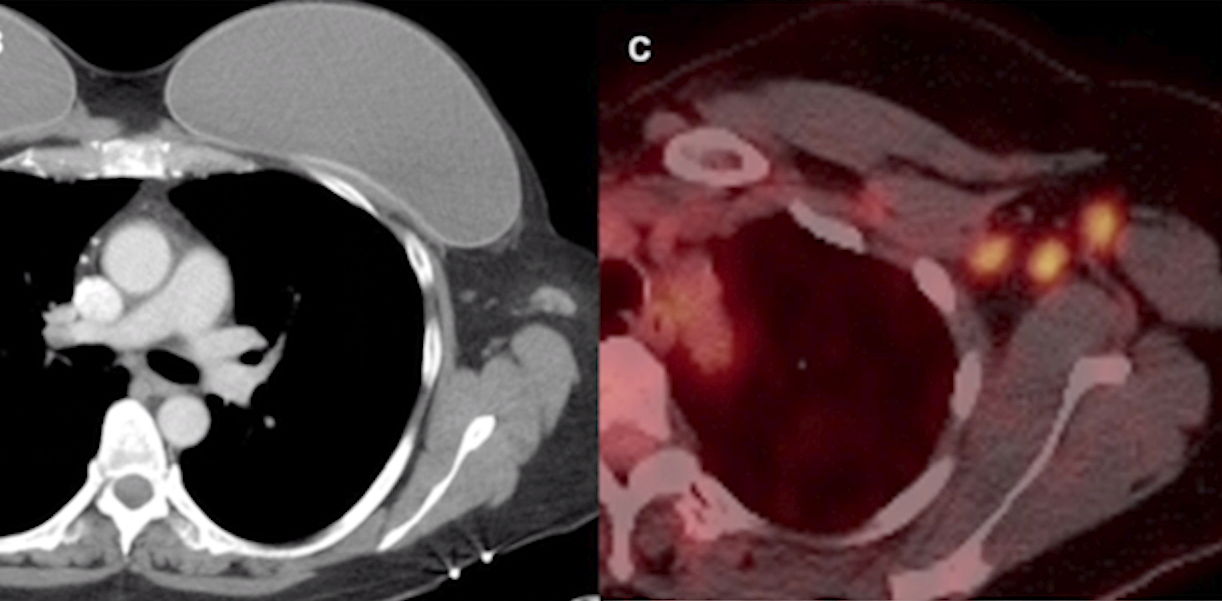

This photo gallery shows the variety of radiological presentations of COVID-19 (SARS-CoV-2) in medical imaging, including computed tomography (CT), radiograph X-rays, ultrasound, echocardiograms and magnetic resonance imaging (MRI). The radiology images show examples of typical COVID pneumonia in the lungs and the numerous complications the virus causes in the body in multiple organs, including the brain, kidneys, heart, abdomen and vascular system.

Ultrasound, especially hand-held ultrasound imaging devices, have become a primary imaging modality for novel coronavirus because of the ease to bag the device and sterilize it after use. CT and mobile X-ray systems are also used as front-line imaging systems for COVID-positive or suspected COVID patients.